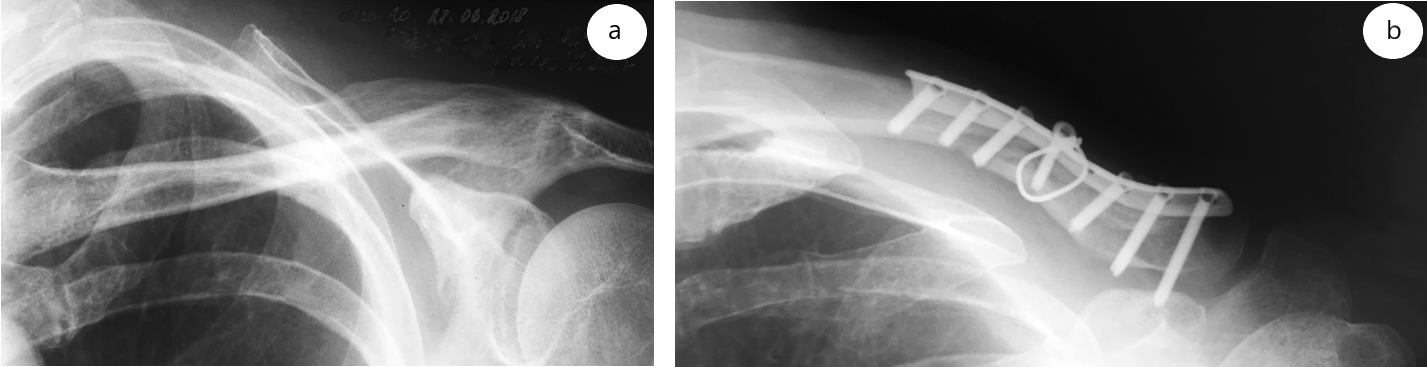

Спустя 4 мес. после подъема тяжести пациент почувствовал резкую боль в области оперативного вмешательства. После проведения контрольной рентгенографии диагностированы несращение ключицы и перелом металлоконструкции (рис. 2).

Рис. 2. Рентгенограмма через 4 мес. после операции: несращение ключицы и перелом металлоконструкции

В другом стационаре пациент вновь был прооперирован: выполнен накостный остеосинтез с использованием костной аутокрошки из большеберцовой кости. Спустя 10 мес., несмотря на попытки медикаментозной и PRP-стимуляции остеогенеза, сформировался гипотрофический ложный сустав левой ключицы (рис. 3).

Рис. 3. Рентгенограмма через 10 мес. после реостеосинтеза: гипотрофический ложный сустав левой ключицы